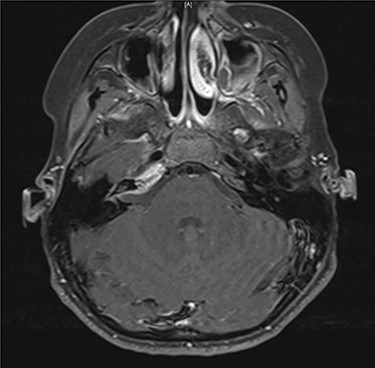

Axial contrast-enhanced T1-weighted image taken 3 months after admission shows enhancement within the right petrous apex and anterior aspect of the internal auditory canal.